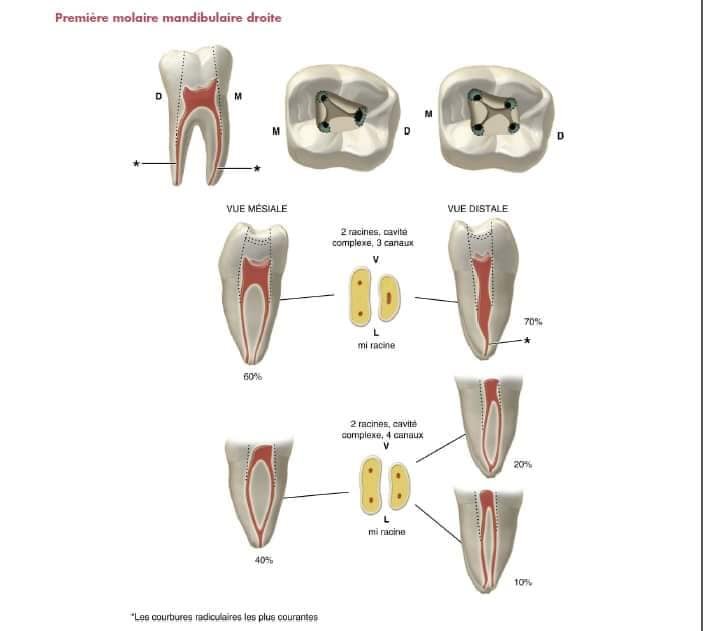

Molaires Mandibulaires

Première Molaire Mandibulaire

Forme : trapézoïdale, grande base mésiale, petite base distale

Position : déportée mésialement

Repérage des cornes :

Corne distale : intersection de la zone neutre (limitée par les sillons vestibulaire et lingual) et l’axe médian de la dent

Corne mésio-linguale : proximité de la fossette marginale mésiale

Corne mésio-vestibulaire : intersection de l’axe (passant par la corne ML et parallèle à la face mésiale) et la pointe cuspidienne MV

Précaution Technique

L’axe de la couronne diffère de celui des racines. Lors de l’approfondissement, tenez compte de l’inclinaison linguale pour éviter une perforation linguale.

Détection d’un Second Canal Distal

Test de la lime :

Si la lime est lâche dans un canal large et centré → un seul canal distal

Si la lime est serrée et s’oriente vers vestibulaire ou lingual → recherchez un second canal dans la direction opposée